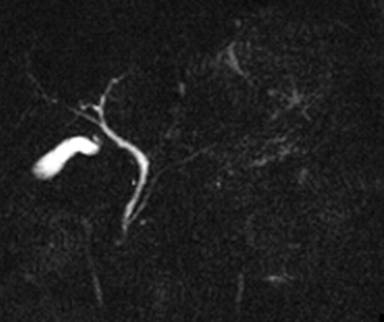

An endoscopy of the upper gastrointestinal tract showed a submucosal tumor, about 4 cm in diameter, located in the posterior wall of the gastric body (Figure 1). The results of the bioptic specimen could not be diagnosed pathologically. MRCP showed neither dilation nor irregularity of the main pancreatic duct (Figure 2). A CT scan demonstrated an ill-defined, irregular solid mass, 6x6x7 cm in size, situated between the retroperitoneum, the pancreas and the lesser curvature of the stomach (Figure 3). The tumor seemed to originate from the retroperitoneum with invasion of the stomach and pancreas. The left gastric artery and the splenic artery were compressed by the tumor which was located adjacent to the celiac axis. Celiac angiography indicated encasement of the splenic artery (Figure 4). Superior mesenteric artery angiography and portography were unremarkable. The tumor was essentially hypovascular. Although a definitive diagnosis was uncertain on the basis of the imaging findings described above, primary neoplasms including malignant mesenchymal tumors were taken into consideration preoperatively.

Figure 2. MRCP showing neither dilation nor irregularity of the main pancreatic duct. |